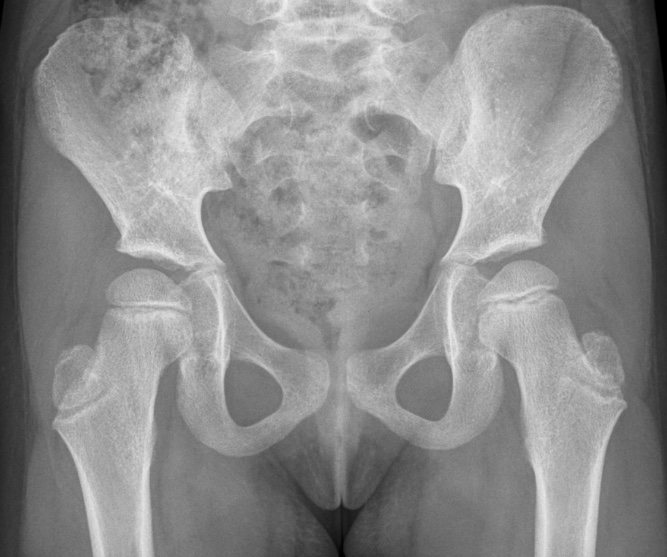

JPM Free FullText Clinical and Radiographic and Treatment Septic Arthritis Treatment Orthobullets On physical exam, the right knee is erythematous,. Septic arthritis in adults is a challenging. Medical history is significant for poorly controlled type ii diabetes mellitus. Aureus should be treated with drainage or debridement and 14 days of intravenous. Acutely swollen or painful joints are common complaints in the emergency department (ed). While monoarticular arthritis can be due to septic. Septic Arthritis Treatment Orthobullets.